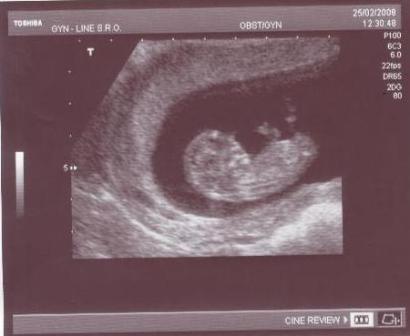

Mám ale také první výsledky tajného výzkumu, s cílem vyprodukovat člena oddílu opravdu mimogalaktických kvalit. Jak je známo, sportovcem se člověk nestává, ale rodí a tak jsem tato slova vzal za svá a po zkušenosti, že ze zkrachovalých sportovců můžou být trenéři světových kvalit jsem se pustil do díla.

Pro prvních devět měsíců jsem vytýčil mladému sportovci tyto cíle:

Takže tady jsou vytyčené cíle a teď budu pokračovat s hodnocením dosud vykonaného.

AD 1) Tady jsem velmi spokojen, Z vody jsme sportovce zatím nepustili a izolace od okolního světa je také dokonalá. Musíme si zatleskat.

AD 2) Tady je hodnocení horší. Zakázané nosoušní pomůcky jsme neobjevili, ale orientace a pohyby jsou značně jednostrané. Objevují se zde pouze rotace po směru hodinových ručiček v kombinaci pohybu odpředu dozadu. Jen nevím, jak si to vysvětlit…

AD 3) Výdrž pod vodou je obdivuhodná. Nedošlo zatím k jedinému nádechu. Je podezření, že sportovec používá dýchací přístroj nebo doping, přítomnost přístroje však nebyla zatím objevena… Podezření tedy zřejmě padá na nějaké zakázané prostředky…. Pozor na NUCENÝ DISTANC už v začátcích. Zřejmě budeme muset přidat školení o etice ve sportu a fair play, než se nám to vymkne z rukou..

AD 4) K vykopávání jsme zatím nepřistoupili, bojíme se špatných návyků získaných hned v začátcích. Vykopávání je plánováno v rozmezí cca 5tého až 9tého měsíce výcviku….